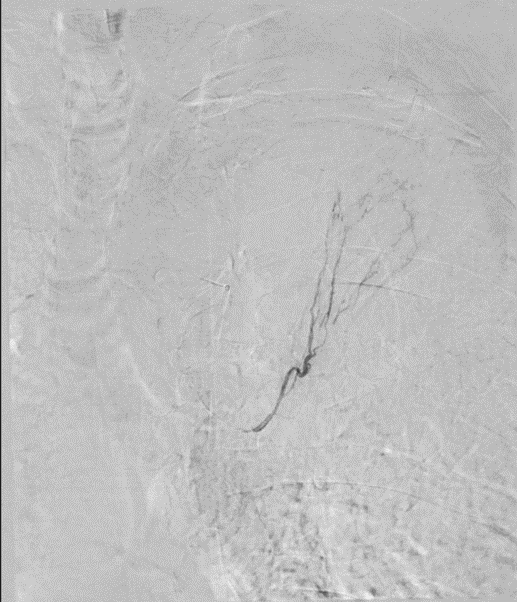

Selective angiogram of the left bronchial artery shows the abnormal arteries supplying the abnormal area .

Embolisation performed using 500 to 700 micron PVA particles. No filling of the abnormal vessels following the procedure with immediate relief in haemoptysis.